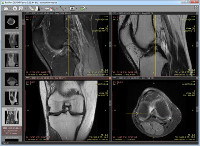

| Cross-reference lines in series with different image planes (e.g., magnetic resonance study)4 |

| 3D cursor tool |

| 2D MPR (orthogonal multiplanar reconstructions) |